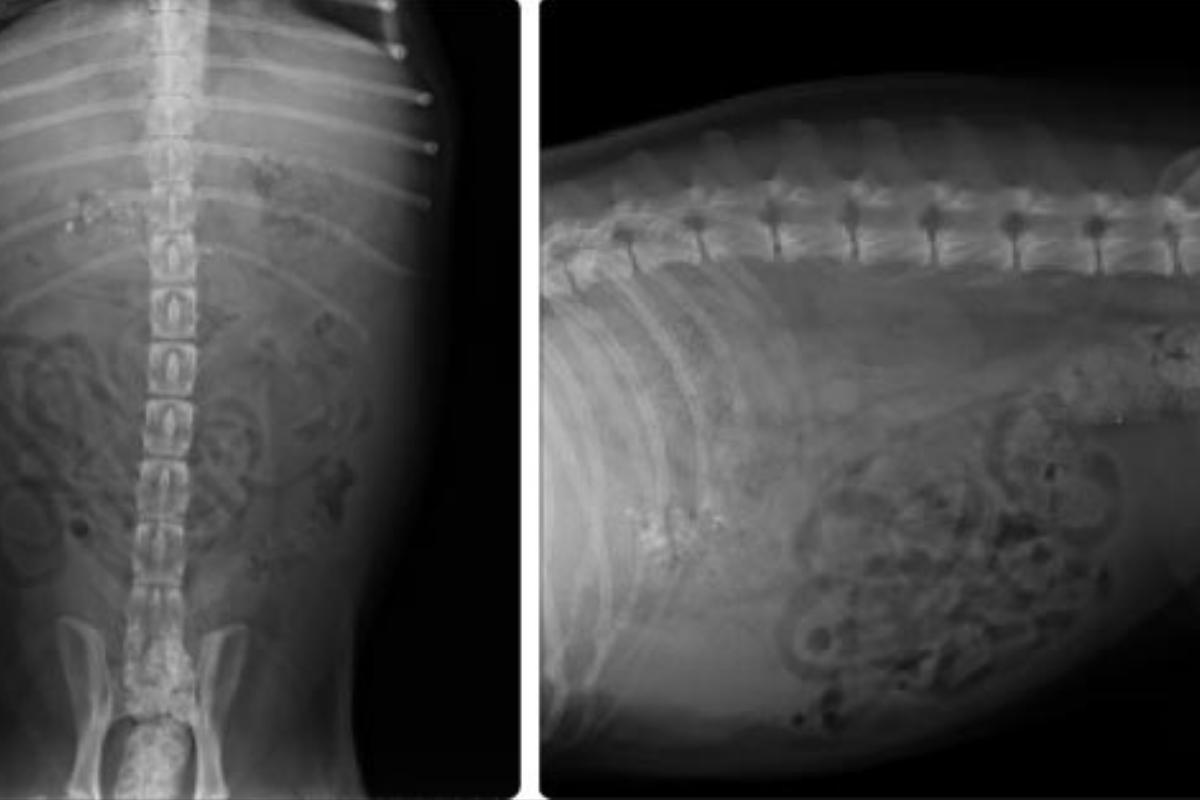

- Radiografías y ecografías: permitirán que se visualice el hígado y la fuga de la bilis.